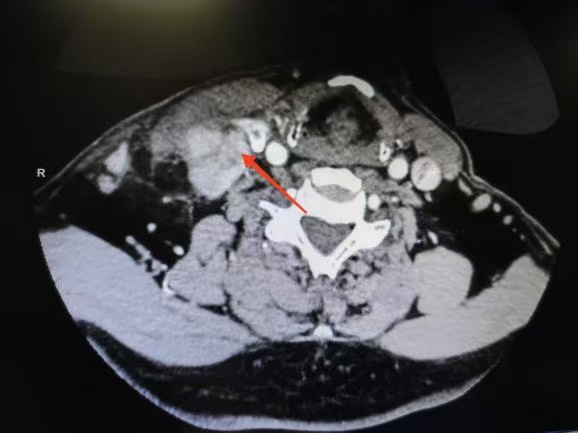

CT箭頭所示:側(cè)頸區(qū)轉(zhuǎn)移淋巴結(jié)

荊楚網(wǎng)(湖北日?qǐng)?bào)網(wǎng))訊(通訊員 楊青青 沈浩元 )近日,孝感市中心醫(yī)院甲狀腺乳腺外科成功為一名67歲男性患者實(shí)施了高難度甲狀腺癌根治手術(shù)。該患者因頸部突發(fā)硬塊4天就診,經(jīng)檢查確診為雙側(cè)甲狀腺乳頭狀癌伴右頸側(cè)區(qū)多發(fā)淋巴結(jié)轉(zhuǎn)移,術(shù)中進(jìn)一步發(fā)現(xiàn)腫瘤已侵犯包繞喉返神經(jīng),側(cè)區(qū)轉(zhuǎn)移淋巴結(jié)亦侵犯頸內(nèi)靜脈,病情復(fù)雜且兇險(xiǎn)。